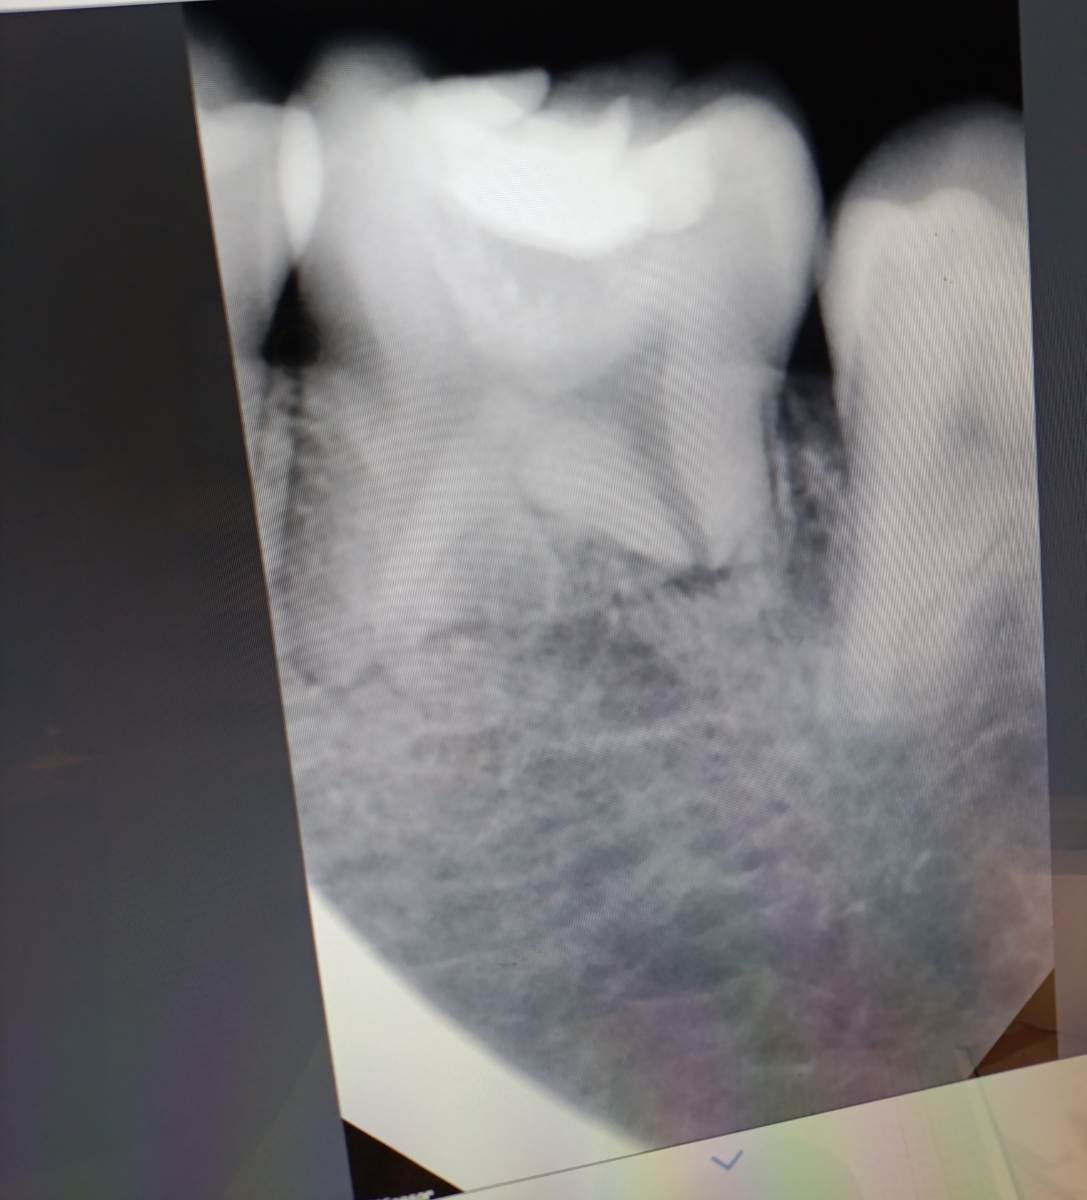

Вадим232311 Опубликовано 14 ноября, 2025 Поделиться Опубликовано 14 ноября, 2025 Добрый день, пришел в стоматологию полечить зуб от кариеса, жалоб на него нет никаких и не было очень долгое время, просто на нем уже достаточно много кариеса. Сделали рентген (вроде 36 зуб), начали рассказывать мне что у меня патология — короткие корни зубов, на противоположном жевательном зубе такой же корень практически. Но по итогу мне так и не сказали есть ли у меня вообще воспаление в корне, но сказали что вылечить такой зуб не получится и его только удалять, но почему я так и не понял. А я просто хотел пломбу поменять( Скажите пожалуйста, есть ли воспаление в корне зуба и можно ли этот зуб перепламбировать? Жалоб на него никаких нет, он мой основной жевательный, болей никаких не было ни разу. Ссылка на комментарий

Вадим232311 Опубликовано 17 ноября, 2025 Автор Поделиться Опубликовано 17 ноября, 2025 В 15.11.2025 в 16:36, Doc сказал: Скорее всего, его можно вылечить. Если удалять все зубы с короткими корнями, зубов не останется. Так а в нем воспаление есть вообще? Один доктор мне сказал что там есть не сильное воспаление, другой доктор сказал что это просто корни рассасываются. Зуб то меня никак не беспокоит Ссылка на комментарий

Doc Опубликовано 18 ноября, 2025 Поделиться Опубликовано 18 ноября, 2025 В 17.11.2025 в 11:07, Вадим232311 сказал: Так а в нем воспаление есть вообще? Один доктор мне сказал что там есть не сильное воспаление, другой доктор сказал что это просто корни рассасываются. Зуб то меня никак не беспокоит Воспаления не вижу. Но тут плоский снимок. Лучше сделать КТ, если есть какие-то вопросы. 1 Ссылка на комментарий